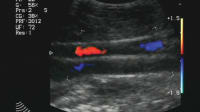

This invention is an ultrasound transducer for the structural characterization of bone. Such characterization measures features of reflected and transmitted ultrasound signals, and correlates these signals with bone structure metrics such as bone mineral density, trabecular spacing, and thickness, etc. The techniques used to determine these various metrics require measurements over a broad range of ultrasound frequencies, and therefore, complete characterization requires the use of several narrowband transducers.

This device consists of a pattern of resonator bars with common electrodes that is wrapped around a central mandrel such that the radiating faces of the resonators are coplanar and can be simultaneously applied to the sample to be measured. The device operates as both a source and receiver of acoustic energy. It is operated by connection to an electronic system capable of both providing an excitation signal to the transducer and amplifying the signal received from the transducer. The excitation signal may be either a wide-bandwidth signal to excite the transducer across its entire operational spectrum, or a narrow-bandwidth signal optimized for a particular measurement technique. The transducer face is applied to the skin covering the bone to be characterized, and may be operated in through-transmission mode using two transducers, or in pulse-echo mode.